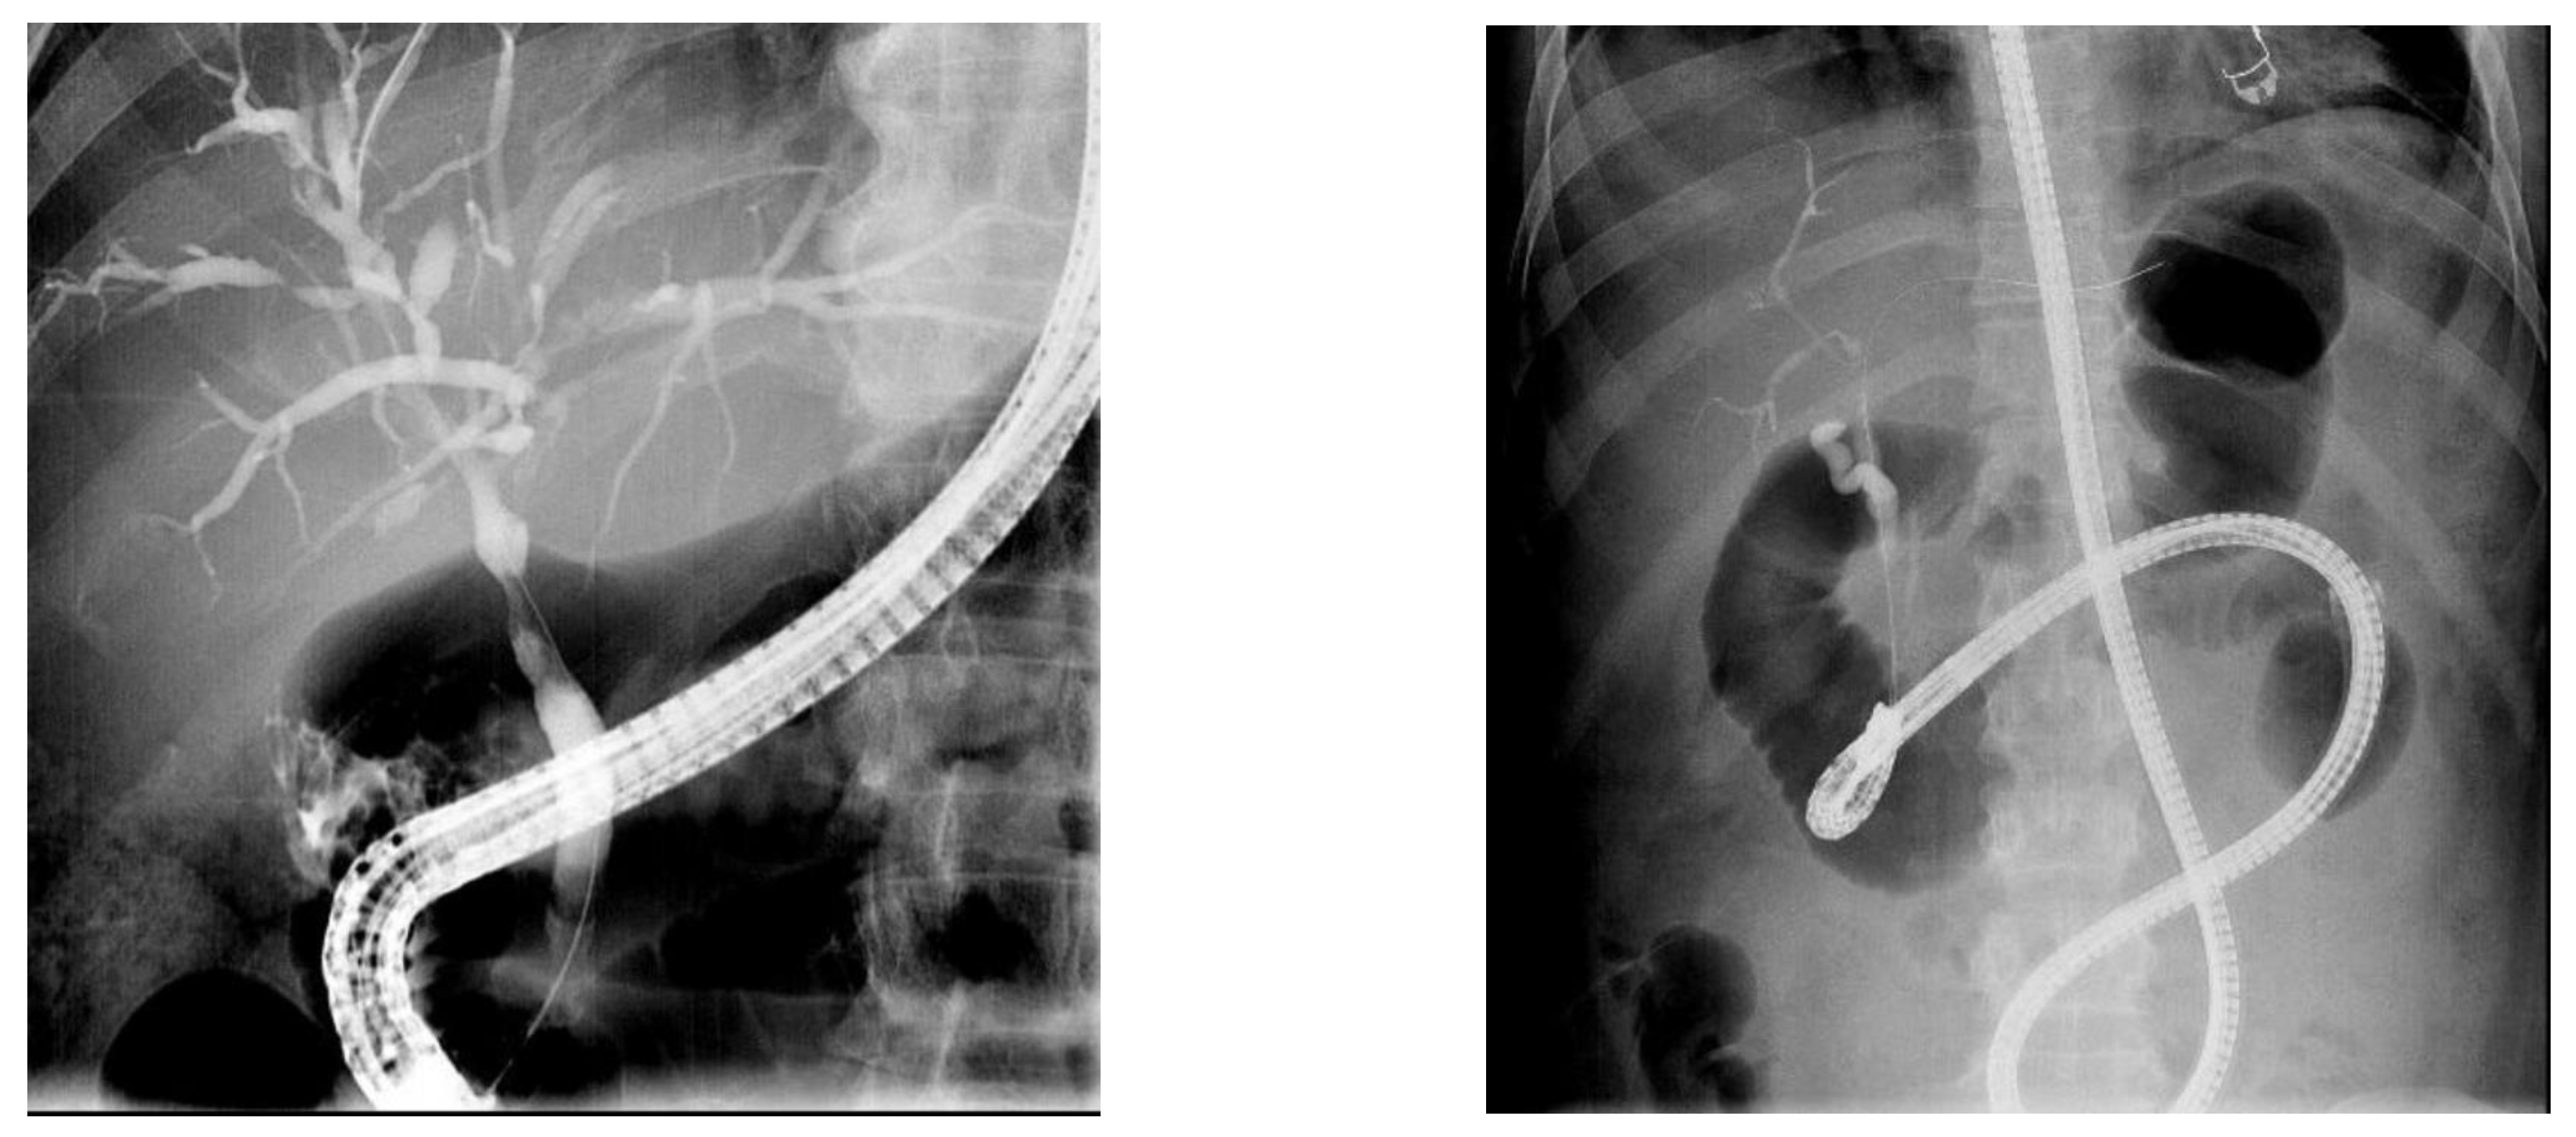

Patient radiation metrics of the C-ERCP group and the EA-ERCP group are shown in Table 2. The total procedure time (endoscope insertion + ERCP procedure) was significantly longer in the EA-ERCP group (77 ± 5 min) as compared to the C-ERCP group (39 ± 3 min, p = 0.0001 Student’s t test), which is mainly explained by the time needed to reach the papilla or the hepaticojejunostomy (28 ± 4 min, ranging from 4 to 90 min) during enteroscope insertion in the EA-ERCP group (Figure 2 and Video S1). The total radiation dose was significantly higher in the C-ERCP group (110 ± 11 mGy) as compared to the EA-ERCP group (83 ± 6 mGy, p = 0.0491 Student’s t test), indicating more complex C-ERCP procedures needing high magnification, whereas the DAP was significantly higher in the EA-ERCP group (2216 ± 173 µGy*m2 vs. 1600 ± 117 µGy*m2, p = 0.0038 Student’s t test). This radiation metric illustrates the use of wide-field fluoroscopy over the entire abdomen without collimation to guide the enteroscope towards and through the biliary or afferent limb during the phase of enteroscope insertion in patients with surgically altered anatomy (Figure 2).

The aforementioned DAP dose reference levels for ERCP procedures only take into account conventional ERCP using a duodenoscope in patients with normal anatomy [5]. In general, the introduction of the duodenoscope is straightforward under endoscopic guidance without the need for additional fluoroscopy [24]. Although EA-ERCP procedures are usually indicated for less complex benign biliary indications like postoperative strictures and bile duct stones, the total procedure time is longer. This is due to the often time-consuming and difficult phase of enteroscope insertion through the intestinal limbs of the surgically altered anatomy, ranging from 4 to 90 min in the current study with a mean of 28 ± 4 min. During this phase of enteroscope insertion, wide field fluoroscopy without collimation is used to identify the correct intestinal limb and to guide the device-assisted enteroscope through the limb and to assess the remaining distance to the papilla or the hepaticojejunostomy, as illustrated in the Video S1. The increased DAP in the EA-ERCP group (22.16 Gy*m2 or 2216 ± 173 µGy*cm2) is explained by this phase of enteroscope insertion with the use of fluoroscopy over the entire abdominal surface without collimation. This abdominal X-ray setting is not used during C-ERCP because fluoroscopic guidance is generally not needed to introduce the side-viewing duodenoscope through the normal upper gastrointestinal tract and to position it correctly at the level of the papilla in the second part of the duodenum. Although significantly higher than in the C-ERCP group, the DAP in the EA-ERCP group is still within the lower end of the acceptable range of dose reference levels suggested by the ESGE for conventional ERCP procedures [5]. However, based on recent studies, there is probably still room for improvement to further reduce radiation exposure thanks to more stringent adherence to the ALARA principle [20,21]. The results obtained in the current study may serve as a starting point to identify DAP dose reference levels in patients with surgically altered anatomy undergoing EA-ERCP using any type of device-assisted enteroscopy. It is currently not known, and probably of less clinical importance, whether DAP significantly varies with the type of surgically altered anatomy. The current study does not allow to differentiate and compare DAP values according to the type of surgically altered anatomy. This would require a higher number of ERCP procedures for each type of surgically altered anatomy. EA-ERCP DAP values should also be compared to radiation metrics of alternative approaches of biliary drainage like interventional endoscopic ultrasound or percutaneous transhepatic drainage or laparoscopy-assisted ERCP.

Figure 2. Fluoroscopic image of a C-ERCP in a patient with normal anatomy for a Klatskin tumor type I with high magnification: antegrade approach (left image). Fluoroscopic image of an EA-ERCP in a patient with Roux-en-Y gastric bypass-altered anatomy without collimation: retrograde approach (right image).